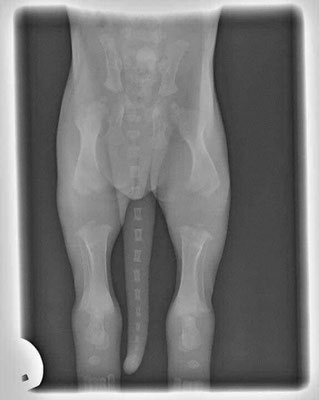

Quando acquistate cuccioli di 8/10 settimane, tenete a mente queste immagini. Le loro ossa non si toccano ancora. Si muovono, così, dolcemente con grandi zampe fluttuanti e movimenti traballanti perché le loro articolazioni sono interamente costituite da muscoli, tendini, legamenti con rivestimento cutaneo. Niente si adatta perfettamente o ha ancora un vero e proprio assetto.

Quando li sottoponete a sforzi eccessivi o non limitate il loro esercizio per impedire loro di esagerare durante questo periodo, non garantite loro la possibilità di crescere correttamente. Ogni grande salto o corsa fuori controllo provoca impatti tra i capi articolari. Un esercizio moderato ed eseguito con razionalità non da problemi.

Quando lasciate che il vostro cucciolo salti su e giù dal divano o dal letto, lo portate a fare lunghe passeggiate / escursioni, state danneggiando le articolazioni. Quando lasciate che il cucciolo scivoli sulle piastrelle senza contenzione adeguata, state danneggiando le articolazioni.

Avete la possibilità di crescerli solo una volta. Un fisico ben costruito è qualcosa che scaturisce da un allevamento di qualità eccellente e da una grande educazione all’esercizio da parte di voi proprietari: in cooperazione.

Una volta che il cucciolo sia cresciuto avrete il resto della vita da trascorrere giocando e impegnandovi in esercizi di maggiore intensità. Quindi mantenete la calma mentre sono ancora cuccioli e fategli un regalo che può essere fatto solo una volta.

Queste sono le lastre di un cucciolo di 2 mesi.

Notate quanto devono crescere ancora le ossa per diventare delle articolazioni finite! Questo è il motivo per cui non dovreste MAI permettere ai cuccioli di saltare, salire e scendere le scale ed esercitarsi troppo.

Svolgere troppe attività che sollecitino le articolazioni in crescita potrebbe causare dei seri problemi ortopedici nel tempo o anche nell’immediato, a giudicare dalla grande quantità di cuccioli che presentano displasie e altri problemi ortopedici.

Ricordate la regola dei cinque minuti: aumentare le attività fisiche di cinque minuti per ogni mese di vita; un cucciolo di 8 settimane non dovrebbe farne più di 10 minuti al giorno, per un cucciolo di 6 mesi ne sarebbero necessari solo 30 minuti; a maggior ragione se il cane è di taglia grossa.

** per attività fisiche si intendono passeggiate, allenamenti, giocare al riporto, correre, ecc.

Godetevi il vostro cucciolo ma ricordate che così come non portereste un bebè di sei mesi a correre una maratona, altrettanto non dovreste fare con il vostro cucciolo.